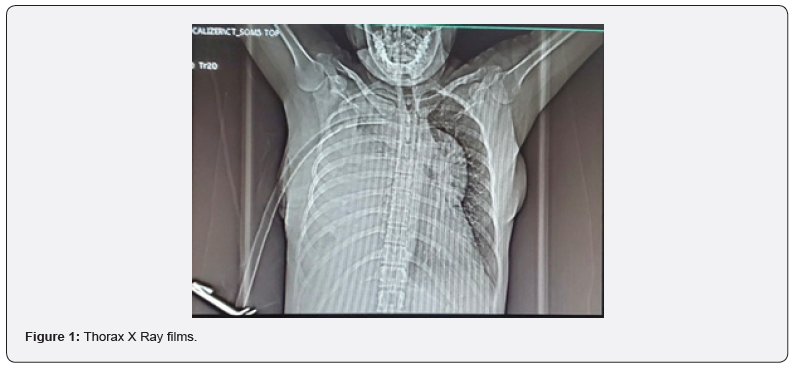

One month later she came to ED in the same health center with the same symptoms, on physical examination there is dullness on percussion on the right hemithorax. The attending physician order an X Ray, and a pleural effusion vs empyema is suspected, a chest tube is placed on the right hemithorax but there is not exudate drain (Figure 1). A CT scan without contrast report liquid density of 100% of right hemithorax UH between 2-38 multiples loculations and septum that produced atelectasis and displaced mediastinal structures. It was not possible to determine the size of the anterior mediastinal mass (Figure 2).

On the emergency anesthesia evaluation, reviewing the images it was determined that the trachea is displaced at principal bronchi level, and unipulmonar ventilation will be necessary, but there is not a direct compromised of the airway.